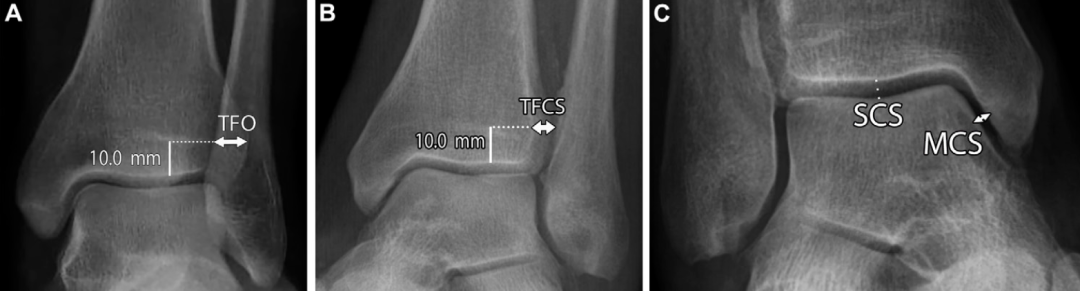

X线摄片是初步评估远端胫腓联合损伤的首选影像学检查方法,对判断骨折、识别胫骨与腓骨远端解剖关系异常具有重要作用。负重位踝关节X线片(包括正位、侧位和踝穴位,踝穴位为小腿内旋15°~20° 的正位片)是检出胫腓联合异常的关键。此外,对可疑病例,需拍摄胫骨和腓骨全长的正侧位 X 线片,以评估近端骨折情况 。

X线片评估胫腓联合分离可通过三项核心测量指标:胫腓重叠距离、胫腓间隙宽度和内侧间隙宽度:

胫腓重叠距离指腓骨远端内侧缘与胫骨远端前结节之间的水平距离,测量点位于胫骨关节面上方10mm处;正位片上该值大于6mm、踝穴位上大于1mm为正常范围 。胫腓重叠距离缺如可能是正常的解剖变异,但踝关节损伤后若出现单侧缺如,应考虑为胫腓联合分离的征象。

胫腓间隙宽度指胫骨后结节外侧缘与腓骨沟最深点内侧缘之间的水平距离,在正位和踝穴位上于胫骨关节面上方10mm处测量,该值≤6mm 为正常;患侧与健侧的胫腓间隙宽度差值≥2mm,可能提示胫腓联合损伤。

内侧间隙宽度指踝关节踝穴位X线片上内踝与距骨之间的距离,该值不应超过4mm,且通常小于或等于距骨穹窿与胫骨平台之间的上间隙宽度。内侧间隙宽度增宽应警惕三角韧带复合体损伤。